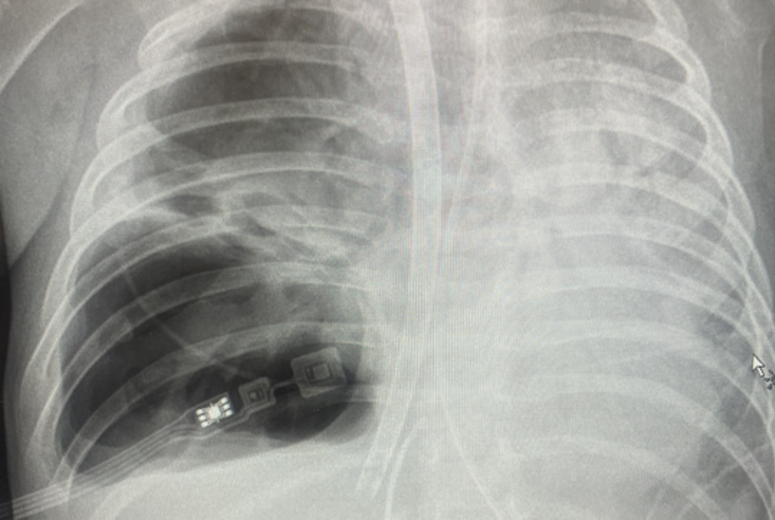

“They took an X-ray and his lungs were all white.”

That night, Charles was admitted to the hospital. Further testing confirmed tuberculosis.

For Charles, ECMO became his lifeline twice. “He was on for two weeks and came off really nicely,” Mirza said. "But the destruction of the lung from tuberculosis caused a cavity in his right lung. We then decided to put him back on ECMO a second time and to collapse his lungs completely for about six to eight weeks."

As Charles remained on ECMO, his lungs slowly began to heal. When doctors reopened them, Mirza said, “his lung no longer had a cavity.”